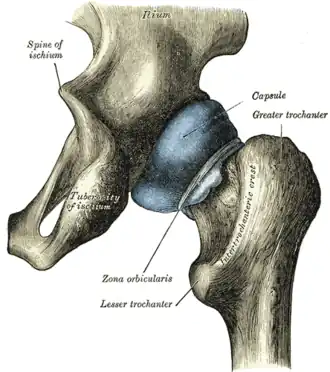

Capsule of hip-joint (distended). Posterior aspect. (Ischial tuberosity visible at bottom left.) | |

Right hip-joint from the front

Right hip-joint from the front -